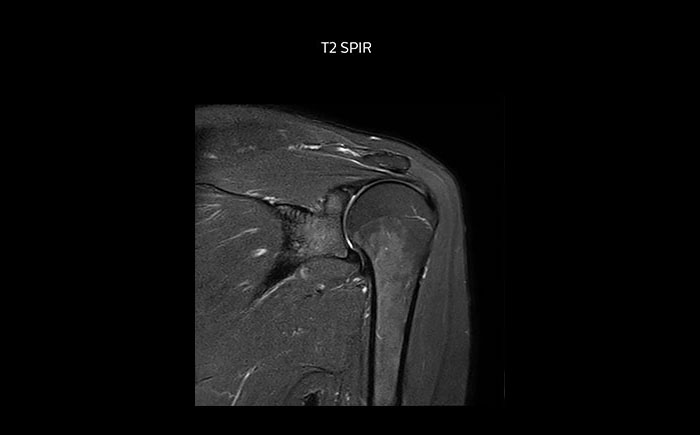

Shoulder MRI with high quality, large coverage

The Prodiva shoulder coil is very flexible and has large coverage, which makes good positioning easier, and that contributes to the superb image quality and high SNR that we get in our shoulder exams.

Scan time 2:55 min, FOV 160 mm, acq voxels 0.55 x 0.83 x 3.0 mm.

Scan time 4:19 min, FOV 160 mm, acq voxels 0.55 x 0.80 x 3.0 mm.

Scan time 2:50 min, FOV 160 mm, acq voxels 0.70 x 0.99 x 3.0 mm.

Shoulder MRI with high quality, large coverage

The Prodiva shoulder coil is very flexible and has large coverage, which makes good positioning easier, and that contributes to the superb image quality and high SNR that we get in our shoulder exams.

Scan time 2:55 min, FOV 160 mm, acq voxels 0.55 x 0.83 x 3.0 mm.

Scan time 4:19 min, FOV 160 mm, acq voxels 0.55 x 0.80 x 3.0 mm.

Scan time 2:50 min, FOV 160 mm, acq voxels 0.70 x 0.99 x 3.0 mm.